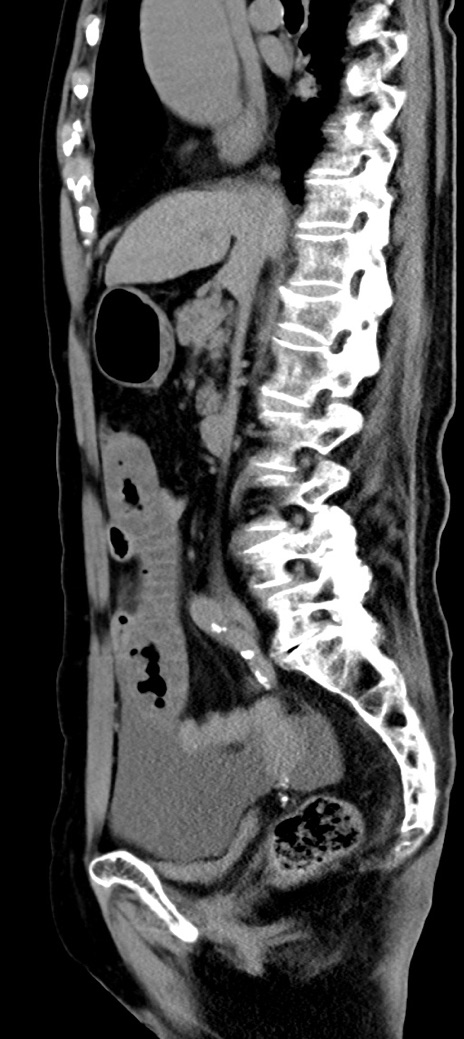

症例40(矢状断像)他院1日前

【症例】90歳代女性

【主訴】腹痛・嘔吐

【現病歴】 食欲低下、嘔吐があり昨日他院受診。肺炎と診断され入院となる。入院後より腹部全体に圧痛あり。胃管留置され経過みていたが、症状持続するため、

当院転院となる。

【既往歴】胸椎圧迫骨折、胆石症

【身体所見】腹部:中央に激痛あり、圧痛あり、反跳痛不明

【データ】WBC 17100、CRP 18.82